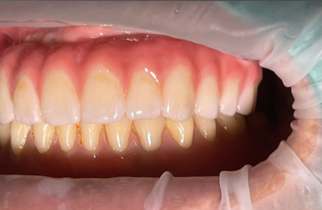

실제 환자분들의 깨끗한 통지르코니아 잇몸 반응